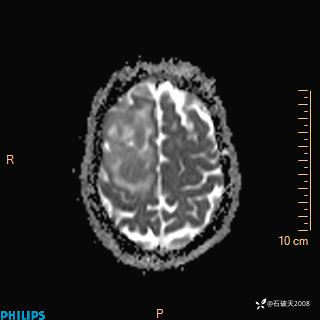

2024.2.21MR

ADC